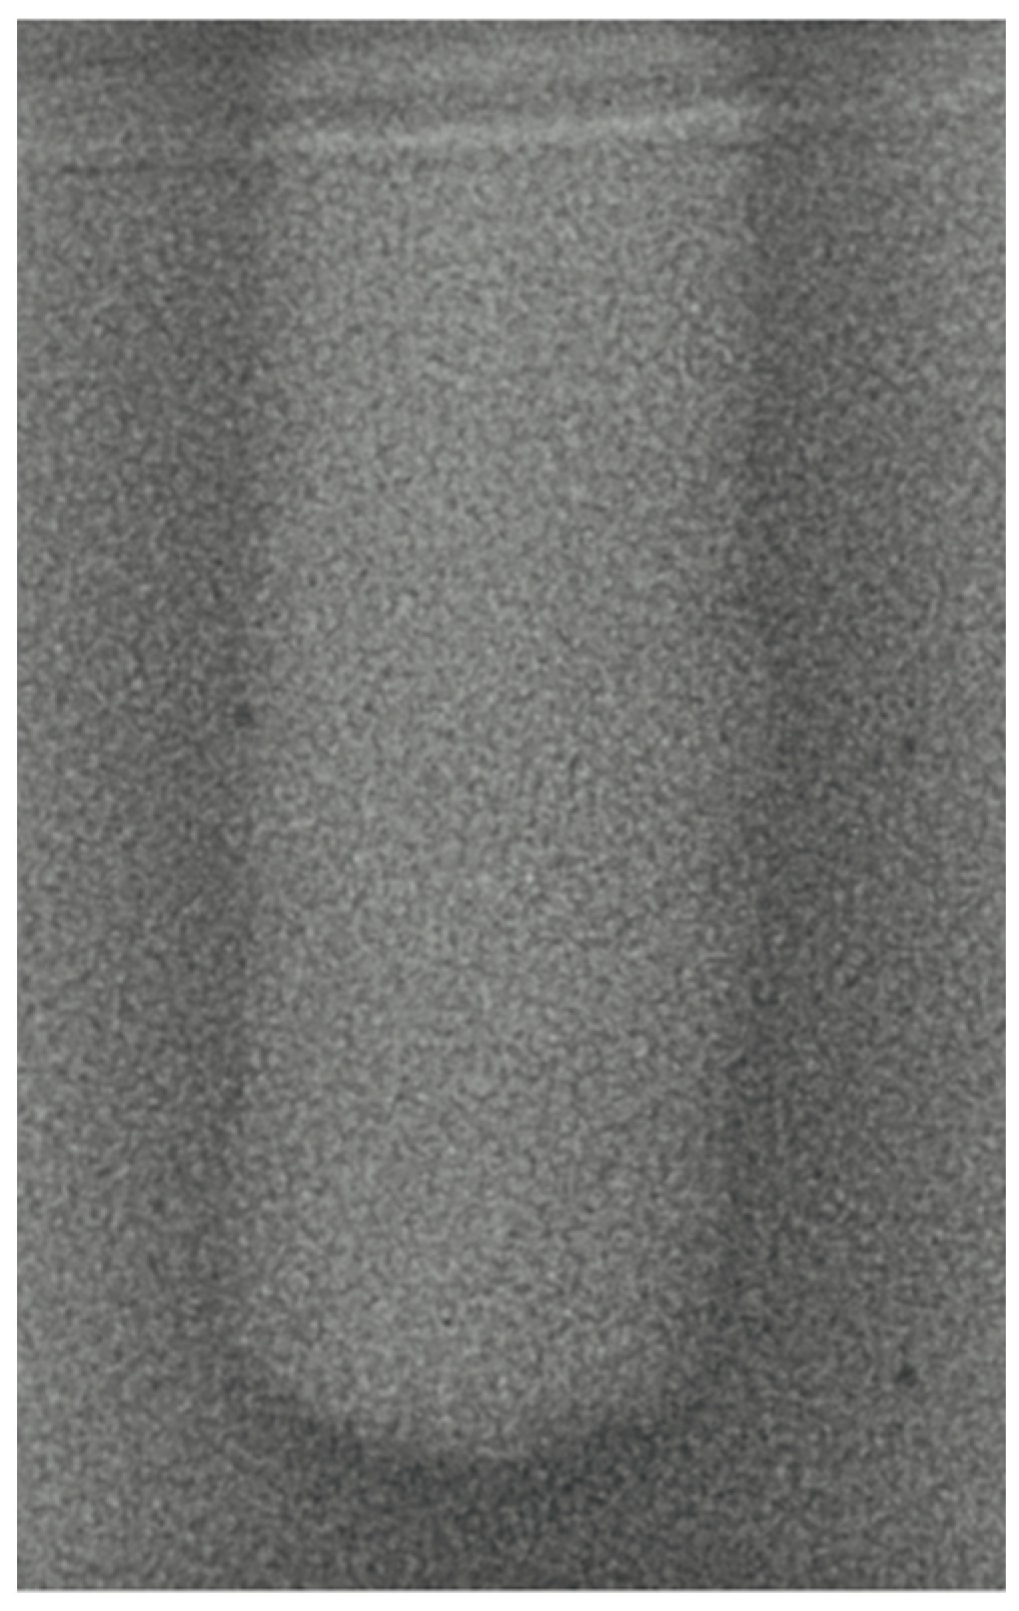

- Vertical effect of magnetic mallet: The forces produced by the MM are transmitted to the tip of the osteotome in order to achieve the plastic deformation of the bone. These forces can affect the bone in three dimensions: horizontally, vertically, and sagittally. However, the vertical effect of the MM goes beyond the area that is in direct contact with the instrument’s tip. By employing a Micro-CT scan, we accurately measured the extent of condensed bone located apically to the preparation site. The results indicate a direct correlation between the size of the condensed area and the density of the bone. Figure 3 shows an implant prepared site employing the MM technique in a bone density of 30 PCF. The length of our preparation measured 11 mm, while the condensed bone resulting from osteotomy extended 3.7 ± 0.14 mm apically to the implant site preparation. By comparing the MM with the other preparation techniques in the same bone density, we observed that, in the sites prepared using the PES approach, the vertical effect of the preparation was noticeably less than that of the MM. It extended apically to the implant site preparation at 0.36 ± 0.08 mm, as shown in Figure 4. When employing the TD technique, we noticed that the vertical effect of this preparation method was minimal compared to the MM and PES, measuring 0.15 ± 0.04 mm, as shown in Figure 5.